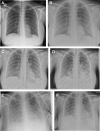

Figures